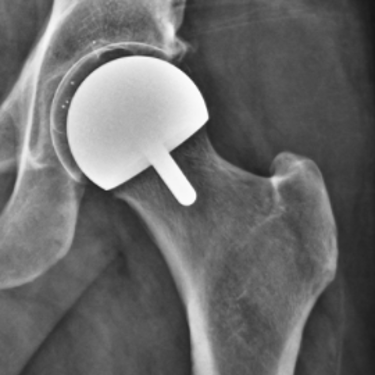

Hip resurfacing is a bone-preserving alternative to total hip replacement, designed for younger, active patients with hip arthritis. Unlike traditional hip replacement, which removes the entire femoral head, hip resurfacing reshapes and caps the existing bone, preserving more of the patient’s natural anatomy.

Hip resurfacing involves placing a metal cap over the reshaped femoral head and lining the hip socket with a metal cup. By preserving the femoral neck and most of the natural bone, this procedure may allow for more natural movement and easier revision if future surgery is needed.